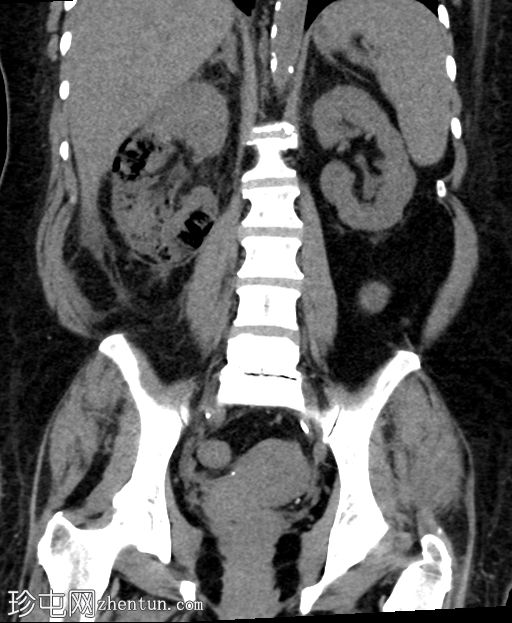

轴位

平扫

肾实质内可见多个气体囊,主要累及右肾中部和下极。

肾周脂肪组织中度炎症性改变,并可见条索状肾周积液。

气体未延伸至肾盂或输尿管。

无肾积水。

少量微小的非梗阻性肾结石(砂砾)。